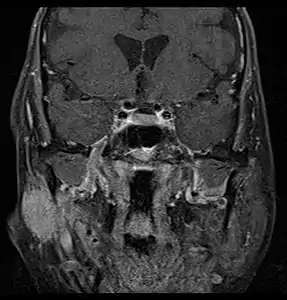

| Parotid gland tumour | |

MRI or CT Scan: These tests can confirm the presence of a tumour. An MRI or CT Scan can also show whether metastasis has occurred.[5]